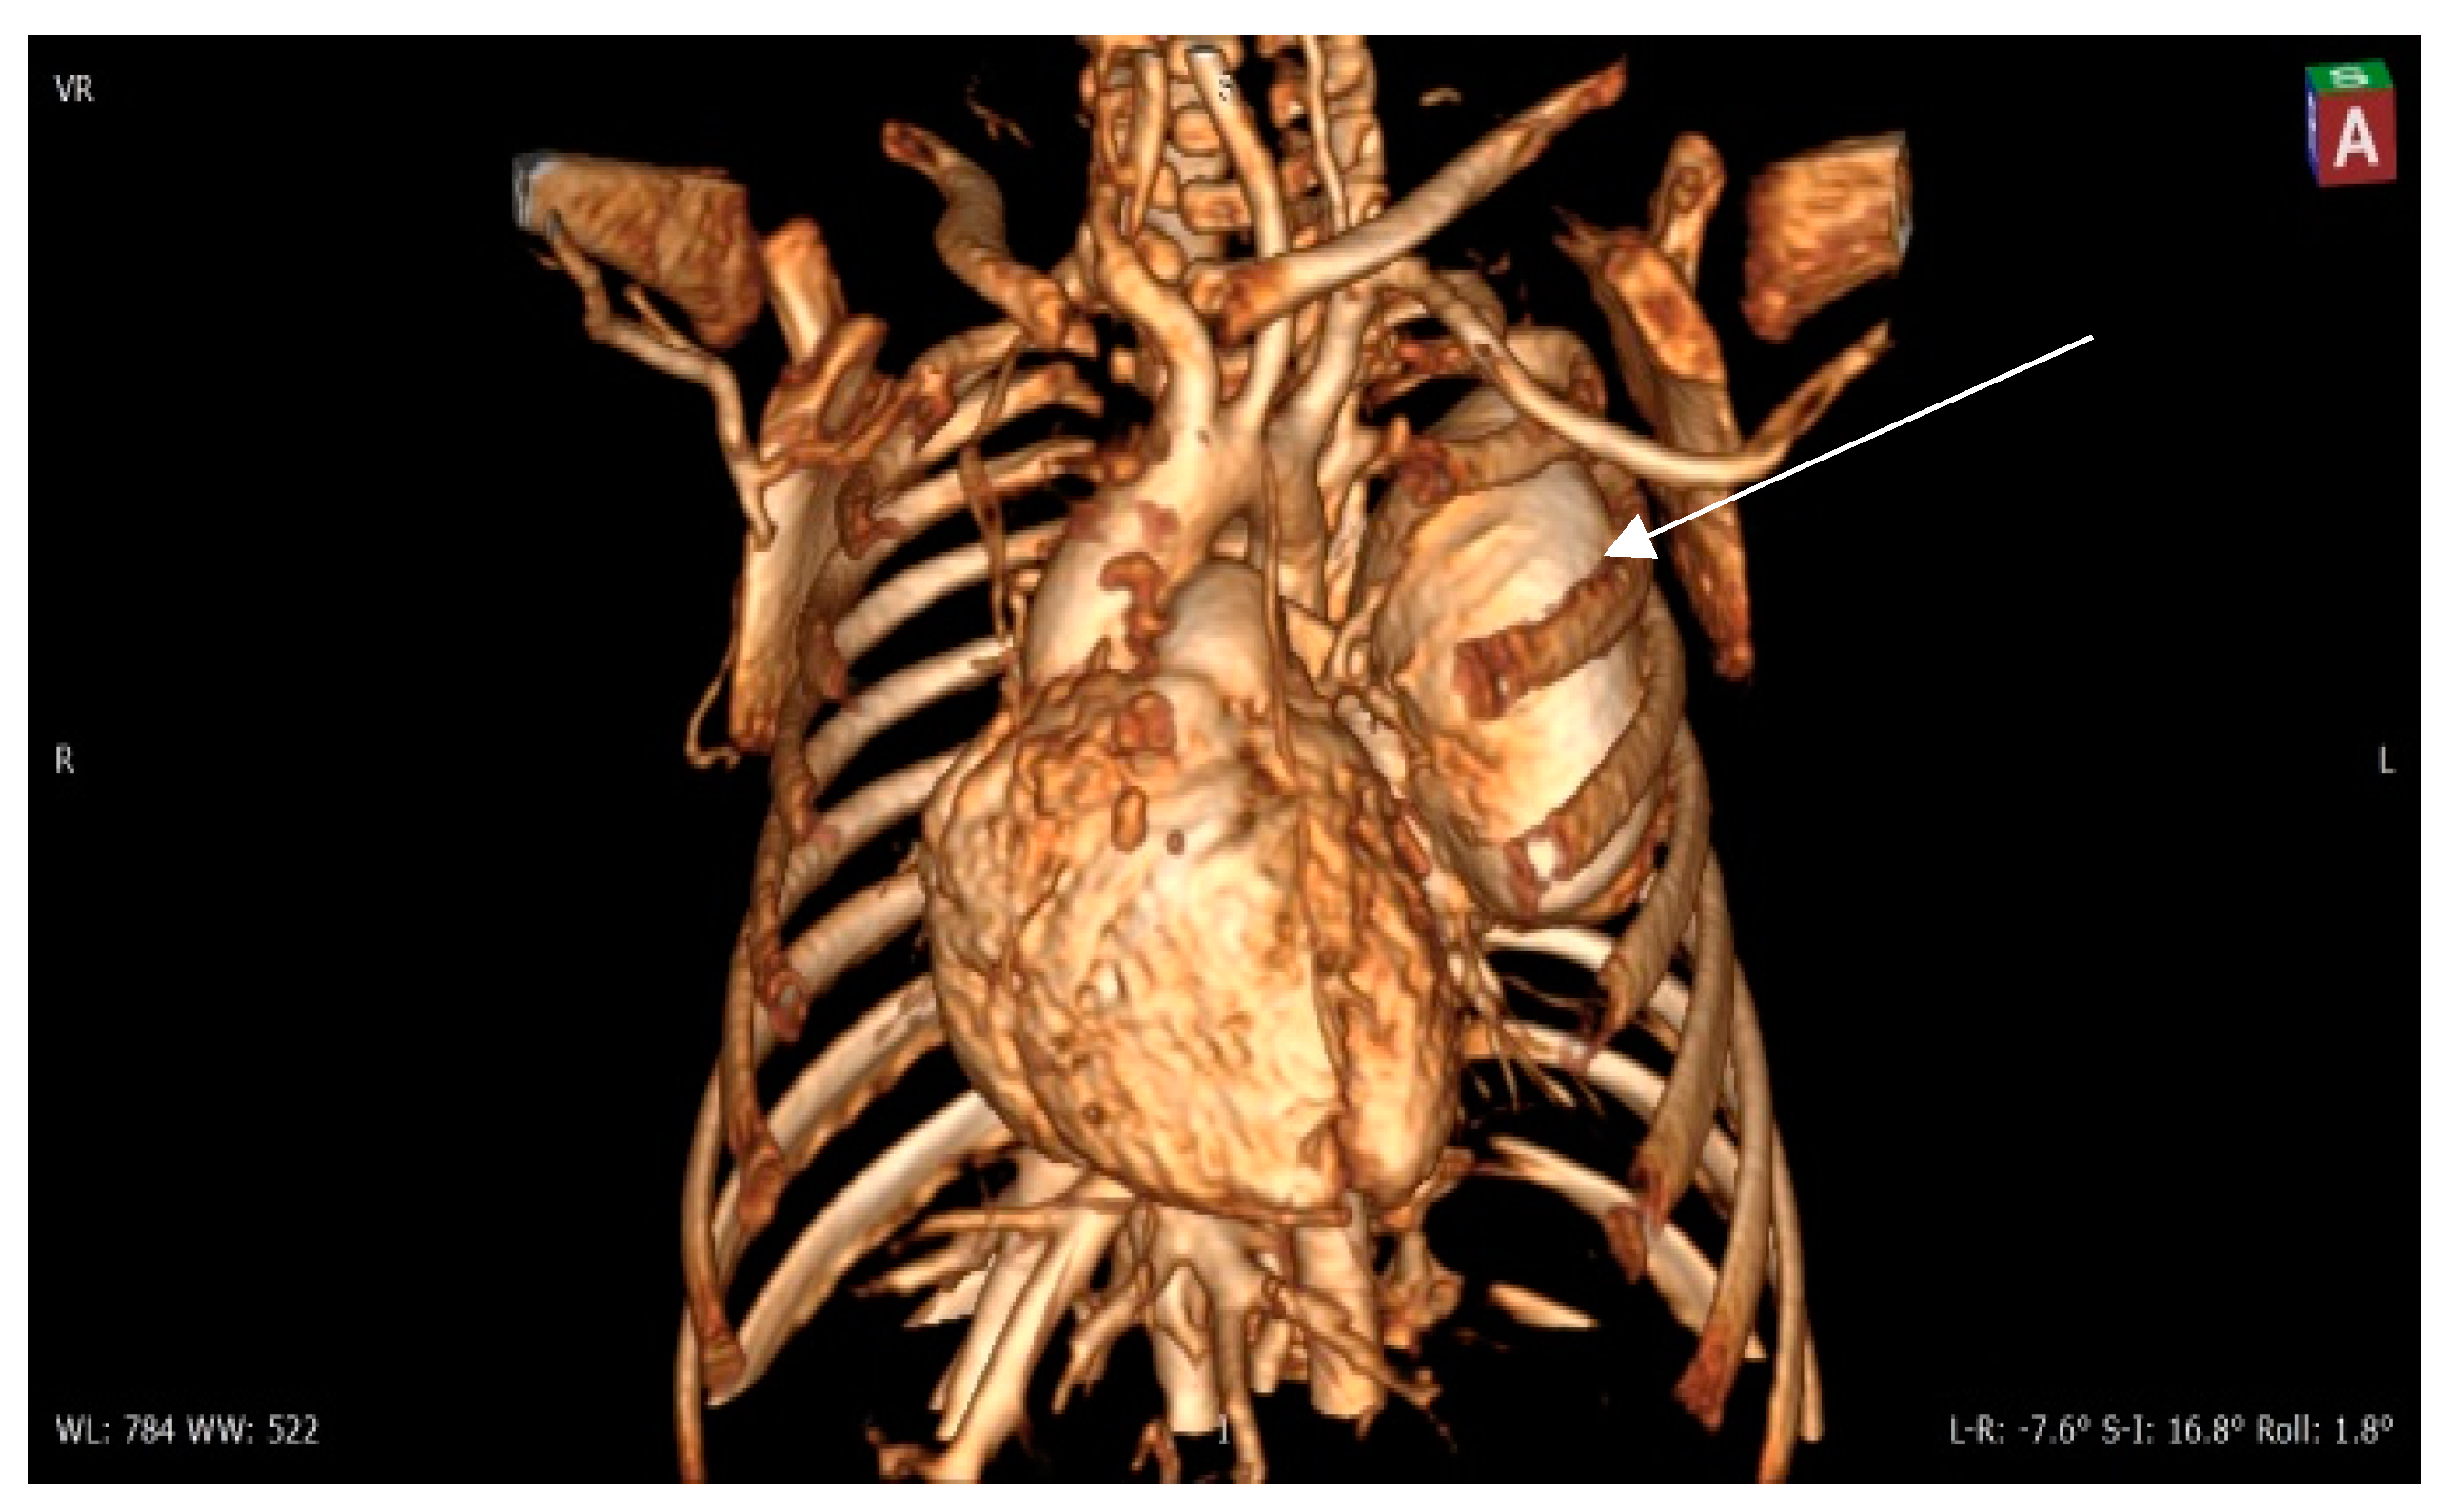

Figure 4. Contrast 3D-CT reconstruction of the structure in the left lung—arrow directed to the PAVM. A rounded formation is present in the left lung constituting the “external manifestation” of the arteriovenous fistula.